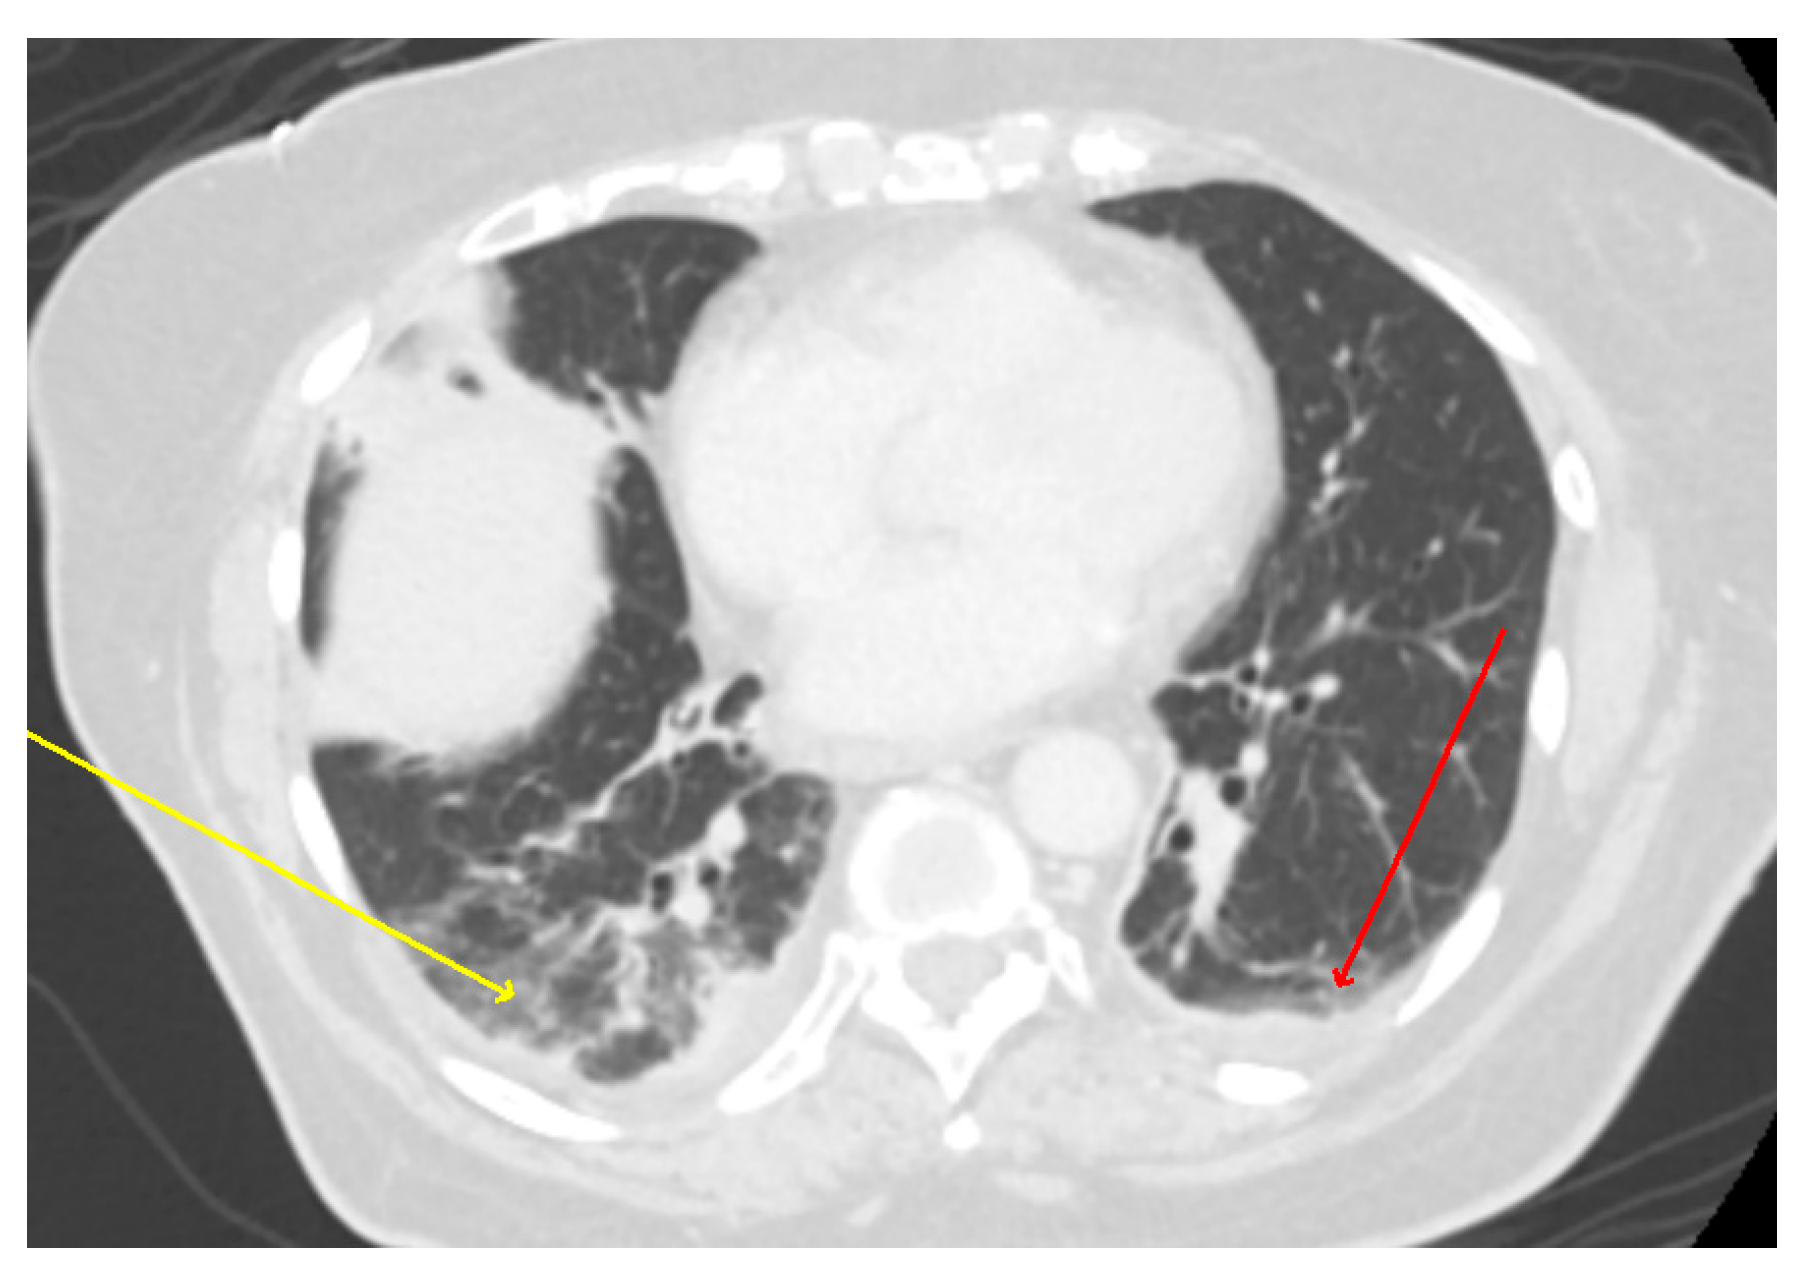

| Patient from this report | 78 | F | USA 2020 | Cough Hypoxia | Bilateral infiltrates and bilateral pleural effusion | DOX (21) | Yes | Improved |